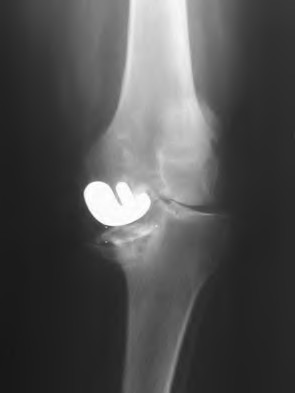

A 65-year-old woman with painful knee arthritis and the deformity seen in Figure A, is scheduled to undergo a total knee arthroplasty. All the following are risk factors for a post-operative peroneal palsy EXCEPT:

Figure A demonstrates and AP radiograph of the knee showing end-stage arthritis with severe lateral compartment narrowing.